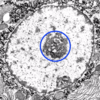

In this hepatocyte, what is the function of the structure enlcosed within the blue circle?

transcription of genes into mRNA; the nucleolus is invloved in the synthesis of rRNA and its assembly into ribosome precursors

In this hepatocyte, what is the structure between 2 yeallow arrows?

heterchromatin